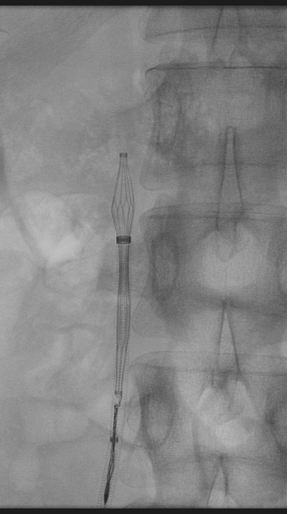

图为:入院后再次尝试腔内回收滤器,经4h努力以失败告终

图为:腹腔镜下腔静脉切开滤器取出